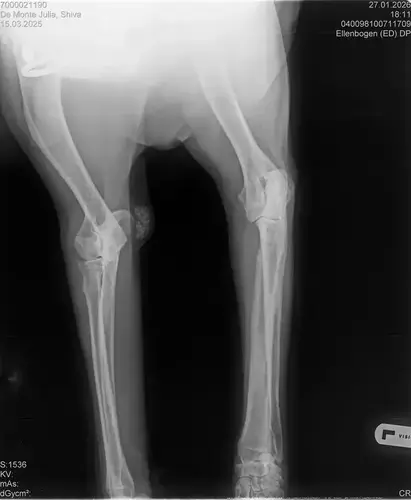

• Naja die Diagnose kommt von einem „Facharzt“, lt TA war ihrerseits alles i.O. Sie wollte noch sicher gehen und die Bilder zur weiteren Befundung einschicken und das kam dabei raus. Und der Therapievorschlag beläuft sich auf Ruhe, Ruhe und noch mehr Ruhe. Und einer Schmertherapie von Gabapentin 800mg 1/2 Tablette 2x tgl, Carprodyl 120mg 1 1/2 Tabletten 1x tgl und TamaCan CBD Tropfen 10-15 Tropfen 2x tgl. 1x in der Woche soll ich telefonisch Auskunft geben wie es Shiva geht. Das ganze mal für 14 Tage. Sie meinte noch sie hat viele Junghunde die ein Leben lang Schmerzmittel nehmem müssten. Die Röhrenknochenentzündung heilt in der Regel von selber der Rest gehört beobachtet… Ich weiß im Moment auch nocht so recht.. Er tut mir nur wahnsinnig leid mit sovielen Diagnosen und für mich war erstmal vorrangig ihn schmerzfrei zu bekommen. Das ist er inzwischen und versteht die Welt nicht mehr warum er nicht wie sonst spielen und arbeiten darf. Im Anhang noch Röntgenbilder falls sich jemand damit auskennt bzw Interesse hat..

• Ok, die Röntgenbilder sind aber auch extrem schlecht.

Panostitis ist idR sehr schmerzhaft, aber nicht unüblich und heilt in der Regel von alleine aus, wichtig dabei ist schonen und Entzündungshemmer zu geben, damit das nicht chronisch wird. Ich denke, dass die Akut bemerkbaren Schmerzen hauptsächlich davon kommen. Also da passt die Empfehlung deiner TÄ für's Erste auf jeden Fall.

Wenn dieser Panostitis-schub rum ist, würde ich dem Rest nochmal nachgehen. Man kann bei Dr. Tellhelm ( SV Gutachter) ein privatgutachten in Auftrag geben, das kostet um die 100€. Da kriegst du halt ne konkrete Einstufung und nicht "verdacht auf" und "könnte hiermit ODER damit in Verbindung stehen", etc.

Ich denke aber, dass du für ein Gutachten von Tellhelm nochmal neu röntgen lassen musst, ich finde, dass das Bild der Hüfte (HD und LÜW wird da beurteilt) und die Draufsicht auf die Ellenbogen (nötig zur Beurteilung von ED) unterirdisch sind!